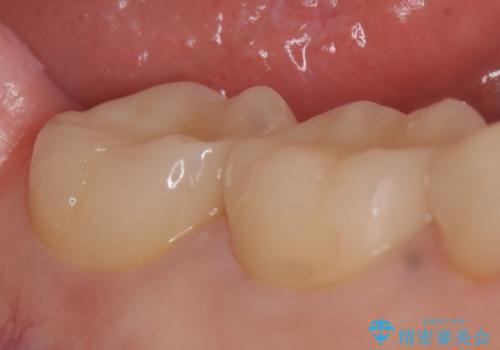

右下6は神経が死んでいたため根管治療を行い、オールセラミッククラウンによる補綴を行いました。

右下7は冷たいものがしみていたため、銀歯を除去後、オールセラミッククラウンによる補綴を行いました。

今回用いたオールセラミッククラウンはジルコニアフレームという白い素材の上にセラミックを盛っているため、審美性が非常に高いのが特徴です。

また、ジルコニアは人工ダイヤモンドの材料にも使われているほど高い強度を持っており、そのためオールセラミッククラウンは審美性だけでなく、奥歯やブリッジの補綴も可能とするクラウンです。